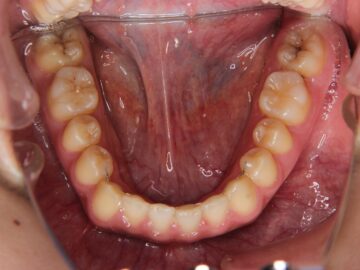

ご相談時

治療後